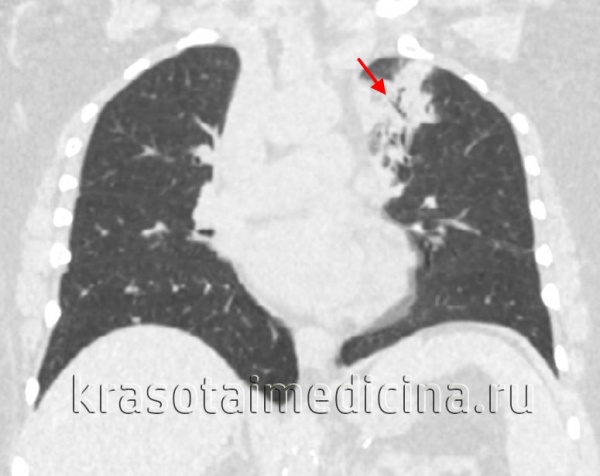

КТ ОГК. Множественные обширные участки снижения пневматизации по типу консолидации в нижних долях обоих легких.